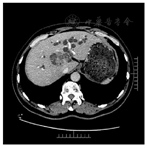

根据"2020 NCCN肝胆癌指南",对于不可切除的胆管细胞癌,首选为全身治疗。对于黄疸患者,在切除和全身治疗前考虑进行胆管引流,胆道减压后考虑行CA19-9基线检查。根据美国癌症联合委员会(American Joint Committee on Cancer,AJCC)第8版肝内胆管细胞癌分期系统,本病例诊断为肝门部胆管细胞癌,T4N1M0 IIIC期,外科评估无法切除(2020年4月30日)。患者因手术未能切除导致疾病进展,7月因胆管梗阻再次入院,检测CA19-9为185.99 IU/ml,TBIL为169.4 umol/L,DBIL为126.8 umol/L。为解决梗阻性黄疸症状,于7月6日行PTCD引流并置入3根引流管。随着部分胆管再通,患者一般情况好转,拟对肝内病灶进行治疗。于10月11日行肝动脉化疗栓塞术(transcatheter arterial chemoembolization,TACE),造影示肝右叶见一团块状浅淡肿瘤染色,主要由肝右动脉供血,术中用药为吉西他滨1.2 g,洛铂50 mg,48%碘化油5 ml。术后予以保肝、退黄等对症处理。 11月复查CT示肿瘤稍有变大,且肝门部及腹膜后可见肿大淋巴结。结合患者病情,建议患者行卡瑞利珠单抗(200 mg静脉滴注,每3周一次)免疫治疗联合阿帕替尼(250 mg口服,1次/d)靶向治疗,患者同意。2020年11月至2021年9月,患者入院接受卡瑞利珠单抗治疗14次,治疗后病灶明显缩小,且液化坏死明显,根据实体瘤改良疗效评估标准(mRECIST)评估为完全缓解(complete remission,CR);其中在2021年5月及2021年9月CT随访中显示肿大淋巴结已明显减小或消失(图5)。CA19-9是胆源性肿瘤关系密切的标志物,CA19-9值的降低能够预测肿瘤大小的减少,可用于潜在地判断对当前治疗的反应[1,2]。此时,CA19-9指标也明显降低并维持正常水平(图6)。